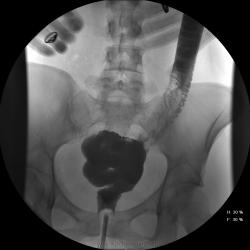

Девушка, 27 лет, жалуется на периодические боли в правой подвздошной области, области паха справа. Во время этого идет нарушение стула - то слабит, то несколько дней не может ходить в туалет, вздутие кишечника. Жалобы несколько лет . Обследованна кем только можно. Хирург посоветовал ирригоскопию. Работа достаточно нервная. До первого случая данных проблем , за неделю, проходила сан лечение в пансионате ( для поднятия общего иммунитета - так говорит), был курс клизм с травами - сама думает, что это не связанно.

В целом -не вижу, к чему придраться, хоть и тонус низковат. Что это? В проекции левого мечеточника. Причем цепочка тенюшек тянется под диафрагму занчительно выше проеции почки?

Цепочка тенюшек - это наша "гордость)" следы от контраста после гистеросальпингоскопии. чтоб вымыть ,надо разбирать стол , а это только с представителем сименса. вот так.) а правые отделы толстой кишки на расширены? я кроме лополнительной петли сигмы сам ничего не вижу. несколько настораживает некоторое расширение правых отделов кишки- может за счет запоров, которые случаются у девушки? не хочется что то пропустить.

Коллеги, значит пишу долихосигма и все?

Считаю, данных за долихосигму нет.

А, чем вызвана неоднородность контрастирования слепой и частично восходящего отдела?

Тугого контрастирования слепой не достигнуто. Должны быть причины.

Слепая кишка в конце исследования, несмотря на её содержимое, заполнилась прилично. А вот гаустрация сигмовидной кишки не сглажена?

Признак долихосигмы - это наличие т.н. симптома "трехстволки", есть это - есть и долихосигма. В данном случае такой вариант имеет место быть.